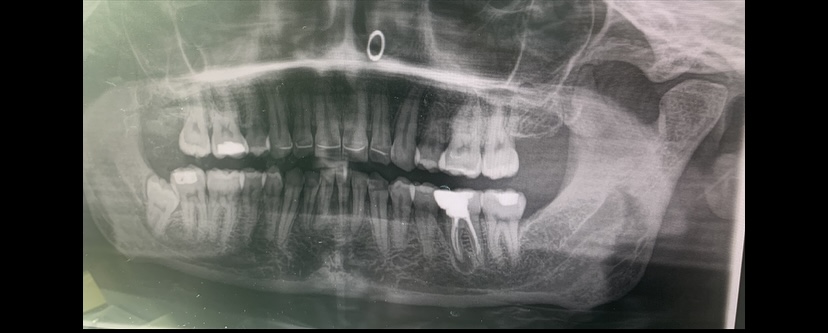

Ik had even een vraagje. Ik ben van de week naar de kaakcirurg geweest en ze hebben een ontsteking in m'n kies gevonden. Nu las ik in het verslag dat dat parodontitis apicalis heet. Ik heb dat gegoogeld en gelezen dat je dan al je tanden kan kwijtraken. Ik ben best wel in paniek en kan pas in januari naar de tandarts vanwege de kosten. En is een foto gemaakt bij de kaakchirug zouden jullie alsjeblieft willen kijken of ik in meerdere tanden parodontitis of botverlies heb? Alvast bedankt.

Parodontitis Apicalis ( apicaal..wortelpunt.) Weet niet waar u gelezen heeft dat u AL uw tanden kunt kwijtraken niet met een parodontitis apicalis wel met parodontitis.. Gezien de foto zou ik mij daar geen zorgen om maken. Ik weet niet of deze kies al door een endodontoloog is her behandeld??. Daar zou ik voor opteren boven een apex resectie wat een KC doet. Dat kan altijd nog indien een herbehandeling zou mislukken.